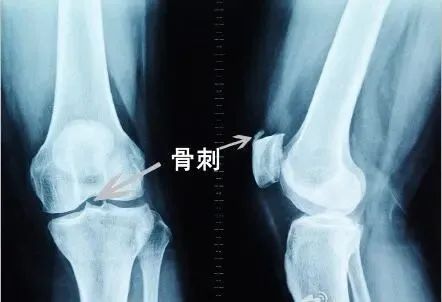

膝关节软骨就会不断磨损变薄

大腿骨和小腿骨之间失去缓冲,骨头碰骨头

就会产生撕心裂肺的疼痛感

骨关节疾病之所以高发

就是因为人体“软黄金”(软骨)在不断退化。

从30岁开始,软骨会变得越来越脆

近八成人的膝关节软骨磨损得只剩一半了

软骨磨损严重者 往往疼得走不了路

研究表明:“痛在关节,根在软骨”。